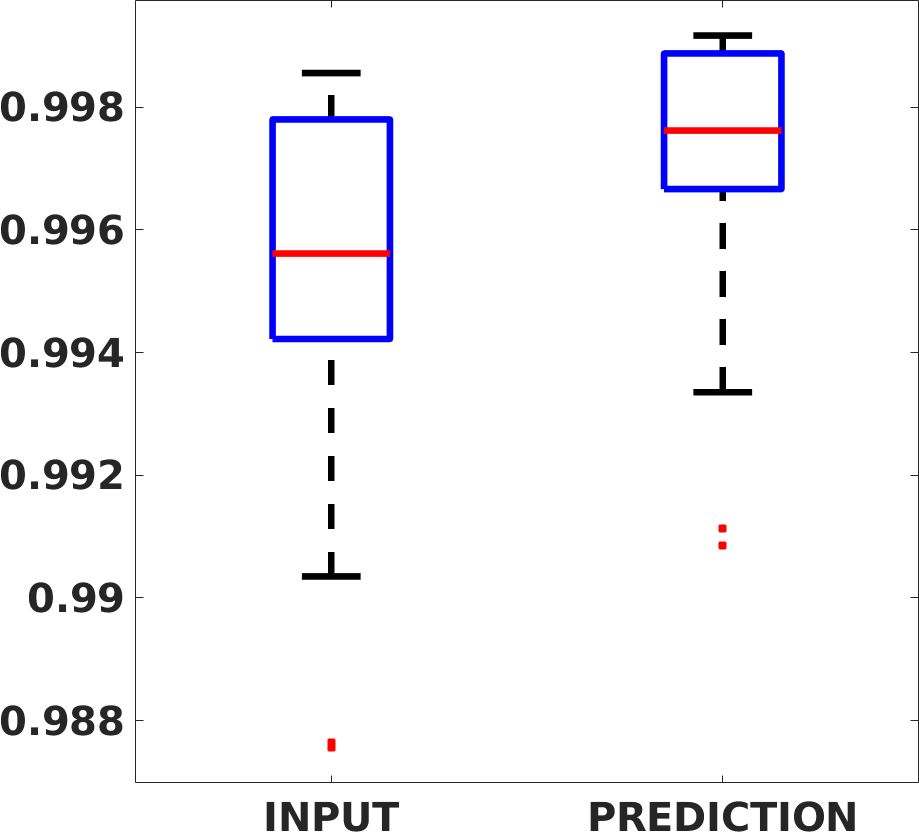

Fig. 7(a-b-c, left) shows the box plot of the statistics of the PSNR on three different anatomical districts, comparing the target images with the prediction and the cubic convolution, respectively. The metrics are computed on a data set of 200 images of the same district and with the same up-sampling factor. We report that the PSNR median value improves of on obstetric 2X raw images, on cardiac 2X raw images, and on abdominal raw 4X images.

Fig. 7(a-b-c, right) shows the histogram of the absolute value of the error with respect to the target image, of the prediction and Cubic convolution results, respectively. The histograms show the number of pixels where the prediction error is lower than 5 (i.e., the first bin of the histogram), which means very similar to the target when visually analysing the images. From the Cubic convolution to the predicted images, this value increases of on obstetric 4X raw images, on cardiac 4X raw images, and on abdominal 4X raw images.

Fig. 8 shows the box plot of the SSIM (a-b-c, left) and MAE (a-b-c, right) quantitative metrics, as performed for PSNR metric. Also, these metrics show that our method improves the results of Cubic convolution both in terms of average value and variability. For example, the SSIM median value improves of on obstetric 4X images and the MAE median value improves of on cardiac 2X images.